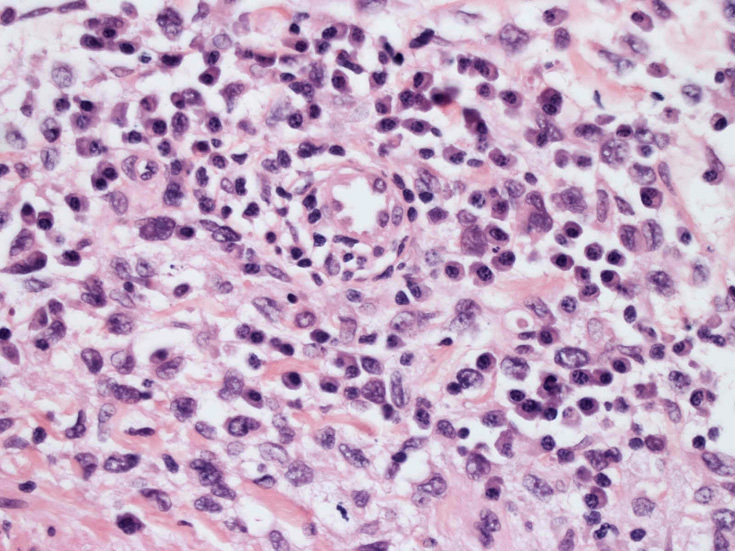

大型細胞の増殖よりなる腫瘍。縦溝,しわ,切れ込みのある核をもった大型細胞も出現する。クロマチンは顆粒状で核小体も明瞭である。核分裂は >50/10hpfと多い。eosinophilsは少ない。壊死が多発することがある。未分化ないし低分化な細胞像, 組織所見のため鑑別診断は多岐にわたり、的確な免疫染色を行う必要がある。

皮膚に異型細胞の浸潤がみられる。異型細胞は表皮内に浸潤するほか、表皮真皮境界部, 真皮, 皮下脂肪組織にもびまん, 結節様の浸潤所見を示す。血管周囲に浸潤、集蔟する所見も多く見られる。 増殖浸潤細胞の核には類円形や腎臓形, またはへこみ, 切れ込み, 溝などを有する多型な核が認められる。クロマチンは粗でvesicularな核が多い。核小体の明らかな核もある。好エオジン性の核内封入体様構造も少数に見られた。mitosisは容易に認められる。hyperchromaticな多型核, bizzarreな細胞が高頻度に認められ異型度は高いと考えられる。細胞質は境界不明瞭, 淡明または泡沫様の 好エオジン性胞体である。

免疫染色 浸潤細胞はCD1a+, S100+, Langerin+, HLA-DR+, CD4+, CD45+, CD68+. MIB-1 index:24.4%

Speaker's Pathological Diagnosis: Langerhans cell sarcoma, skin, rt. knee, biopsy